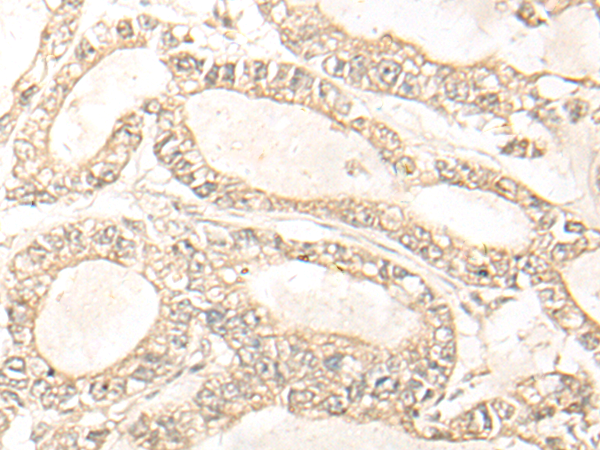

分类: 科研抗体货号: P09631别名: ELA3; ELA3A应用: IHC反应种属: Human